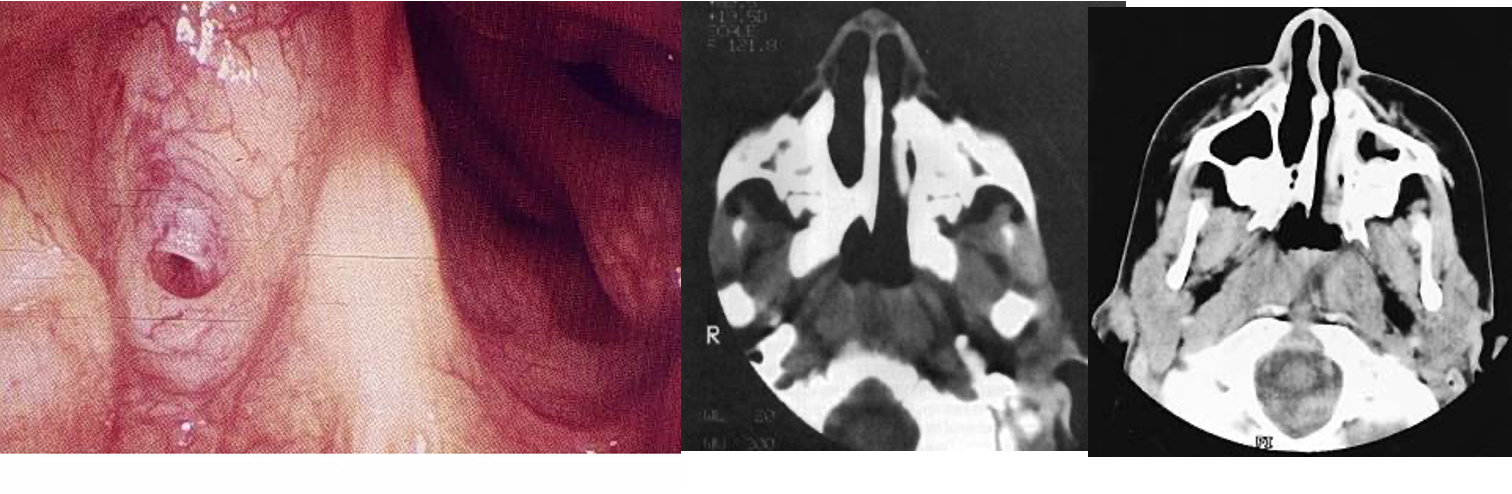

Bilateral Choanal Atresia

-

Isolated anomaly in 60-70%

May be linked to CHARGE association

- Heart disease

- Atresia

- Retarded growth

- Genital hypoplasia

- Ear deformity

Usually presents at birth by attacks of cyclic cyanosis and respiratory obstruction

Nasal discharge

Diagnosis

- Clinical examination: “mirror test”

- Inability to pass a catheter into the nasopharynx

- Endoscopy

- Radiographs

Management

A) Emergency

- Immediate airway support with oral airway, McGovern nipple, or intubation

B) Definitive Surgery Z

C) Surgical Approaches to the Choana Y

- Transnasal

- Transpalatal

- Transseptal

- Lateral rhinotomy

- External rhinoplasty